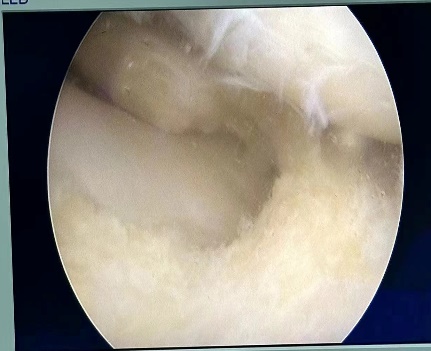

病例七:患者,女,36岁,因“左膝关节疼痛活动受限5天”入院。诊断:左膝外侧半月板撕裂;行左膝关节镜探查+滑膜清理+外侧半月板成形术;手术顺利,术后恢复良好,顺利出院。

左膝外侧半月板撕裂 术中关节手术图片